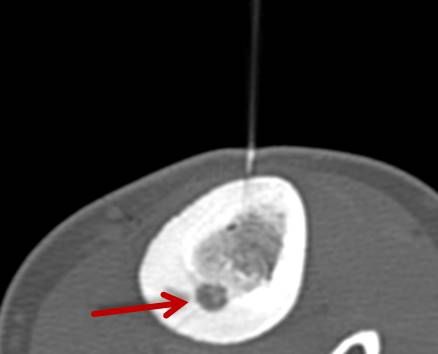

RFA zur Therapie des Osteoidosteoms

Das Osteoidosteom ist ein gutartiger, jedoch sehr schmerzhafter Knochentumor, der bevorzugt bei jüngeren Patienten auftritt. Die Radiofrequenzablation (RFA) hat sich in den letzten Jahren zu einer zuverlässigen, minimalinvasiven Therapieoption bei der Behandlung des Osteoidosteoms entwickelt und wird seit über 15 Jahren an der Uniklinik Tübingen angewandt.

Abbildung: Osteoidosteom (Pfeil) im Schienbein bei einem jungen Patienten. Unter CT-Bildgebung wird ein spezieller Applikatoren unter CT-Bildgebung in das Osteoidosteom eingebracht. Durch Hitze wird dieses effektiv und dauerhaft zerstört.